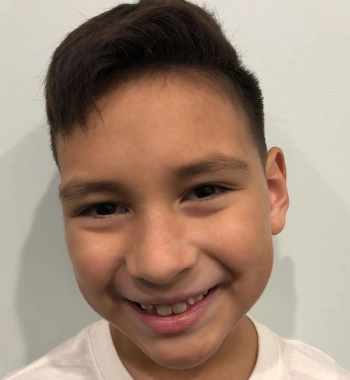

Actual Patient: Carlos

Before

Severe crowding, narrow jaws, severe Deep Bite

Front View

Top View

Right & Left Sides